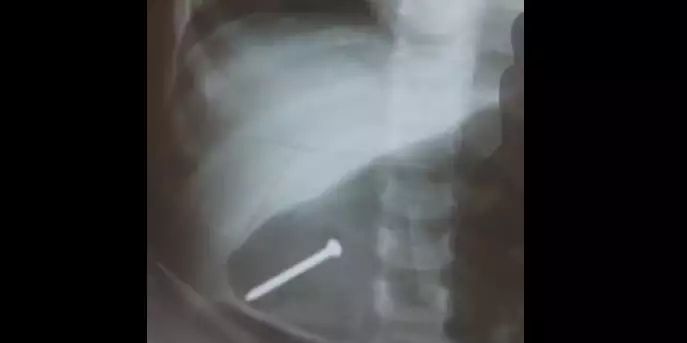

Os familiares relataram que tudo ocorreu rapidamente. A menina estava no chão e teria se engasgado com algo. Os pais desconfiaram que ela teria engolido algum objeto e a levaram para a UPA médico. Na unidade, foi feito um raio-x, que mostrou o prego no estômago na bebê.

A casa onde a menina vive com os pais está em reforma e teria sido limpa, mas o prego não teria sido visto pelos adultos. Os familiares relataram que a bebê teve que ser nutrida somente com soro na veia nos dias que ficou internada em Breves, devido ao risco do prego perfurar algum órgão. Ainda não há mais informações sobre o estado de saúde da menina após dar entrada no pronto socorro em Belém.